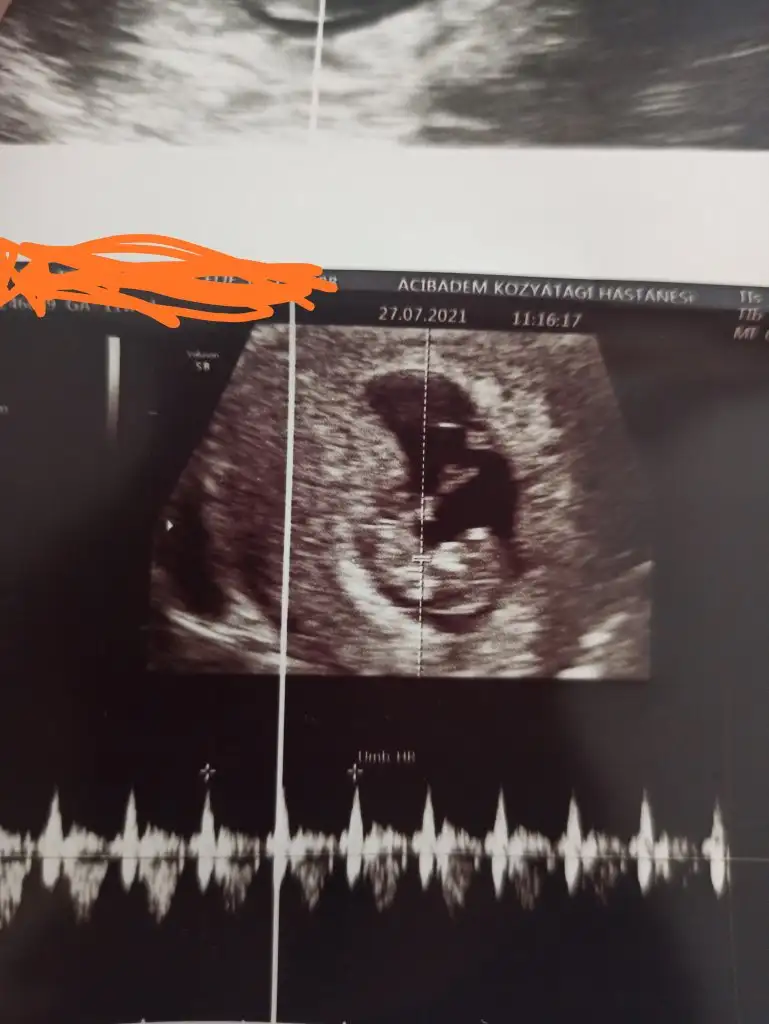

12+6 haftalık hamileyim cinsiyet tahmininiz nedir ?Erkek görünüyor![]()

Erkek gibi ama başka usg olursa paylaşınsevgiliIkra meyra bizimkine de bakar mısın? ne göreceksin çok merak ediyorum, teşekkürler :) 11 hafta ultrasonu.

Sırtı dönmüş12+6 haftalık hamileyim cinsiyet tahmininiz nedir ?![]()

aynı günden bunlar da var ama daha net olanları seçmeye çalışmıştım :)Erkek gibi ama başka usg olursa paylaşın![]()

12-13 hafta olursa paylasin net değilaynı günden bunlar da var ama daha net olanları seçmeye çalışmıştım :)